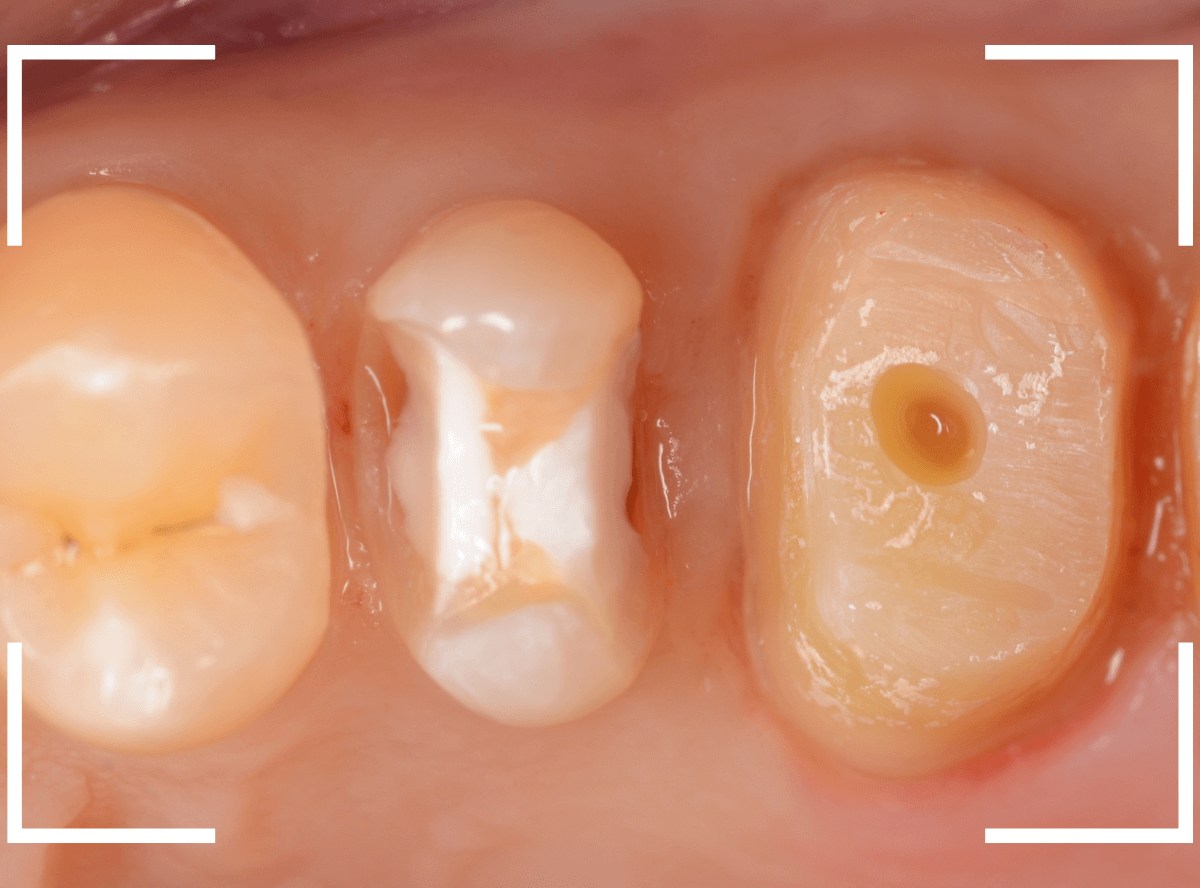

今回は、金属のつめもの(メタル・インレー)の下が虫歯になってしまった方をジルコニア・インレーで治療し直したケースです。

レントゲン写真で確認します。

金属の中と、隣の歯も虫歯になっているのがわかります。

金属を外して、中を確認します。

こういった場合は、下敷きになっているセメントの下も虫歯になっている事が多いので、セメントを全て外して虫歯になってないか、調べます。

う蝕検知液で確認しながら、虫歯を除去します。

このセメントは神経に近い所まで埋まっていますので、削りすぎないように慎重に除去します。

全ての虫歯を除去する事ができました。

しばらく経過観察した後、特に症状もありませんでしたので、歯をトリミングして、型を取ります。

治療前後の比較です。

比べてみると、白い歯の良さがわかると思います。